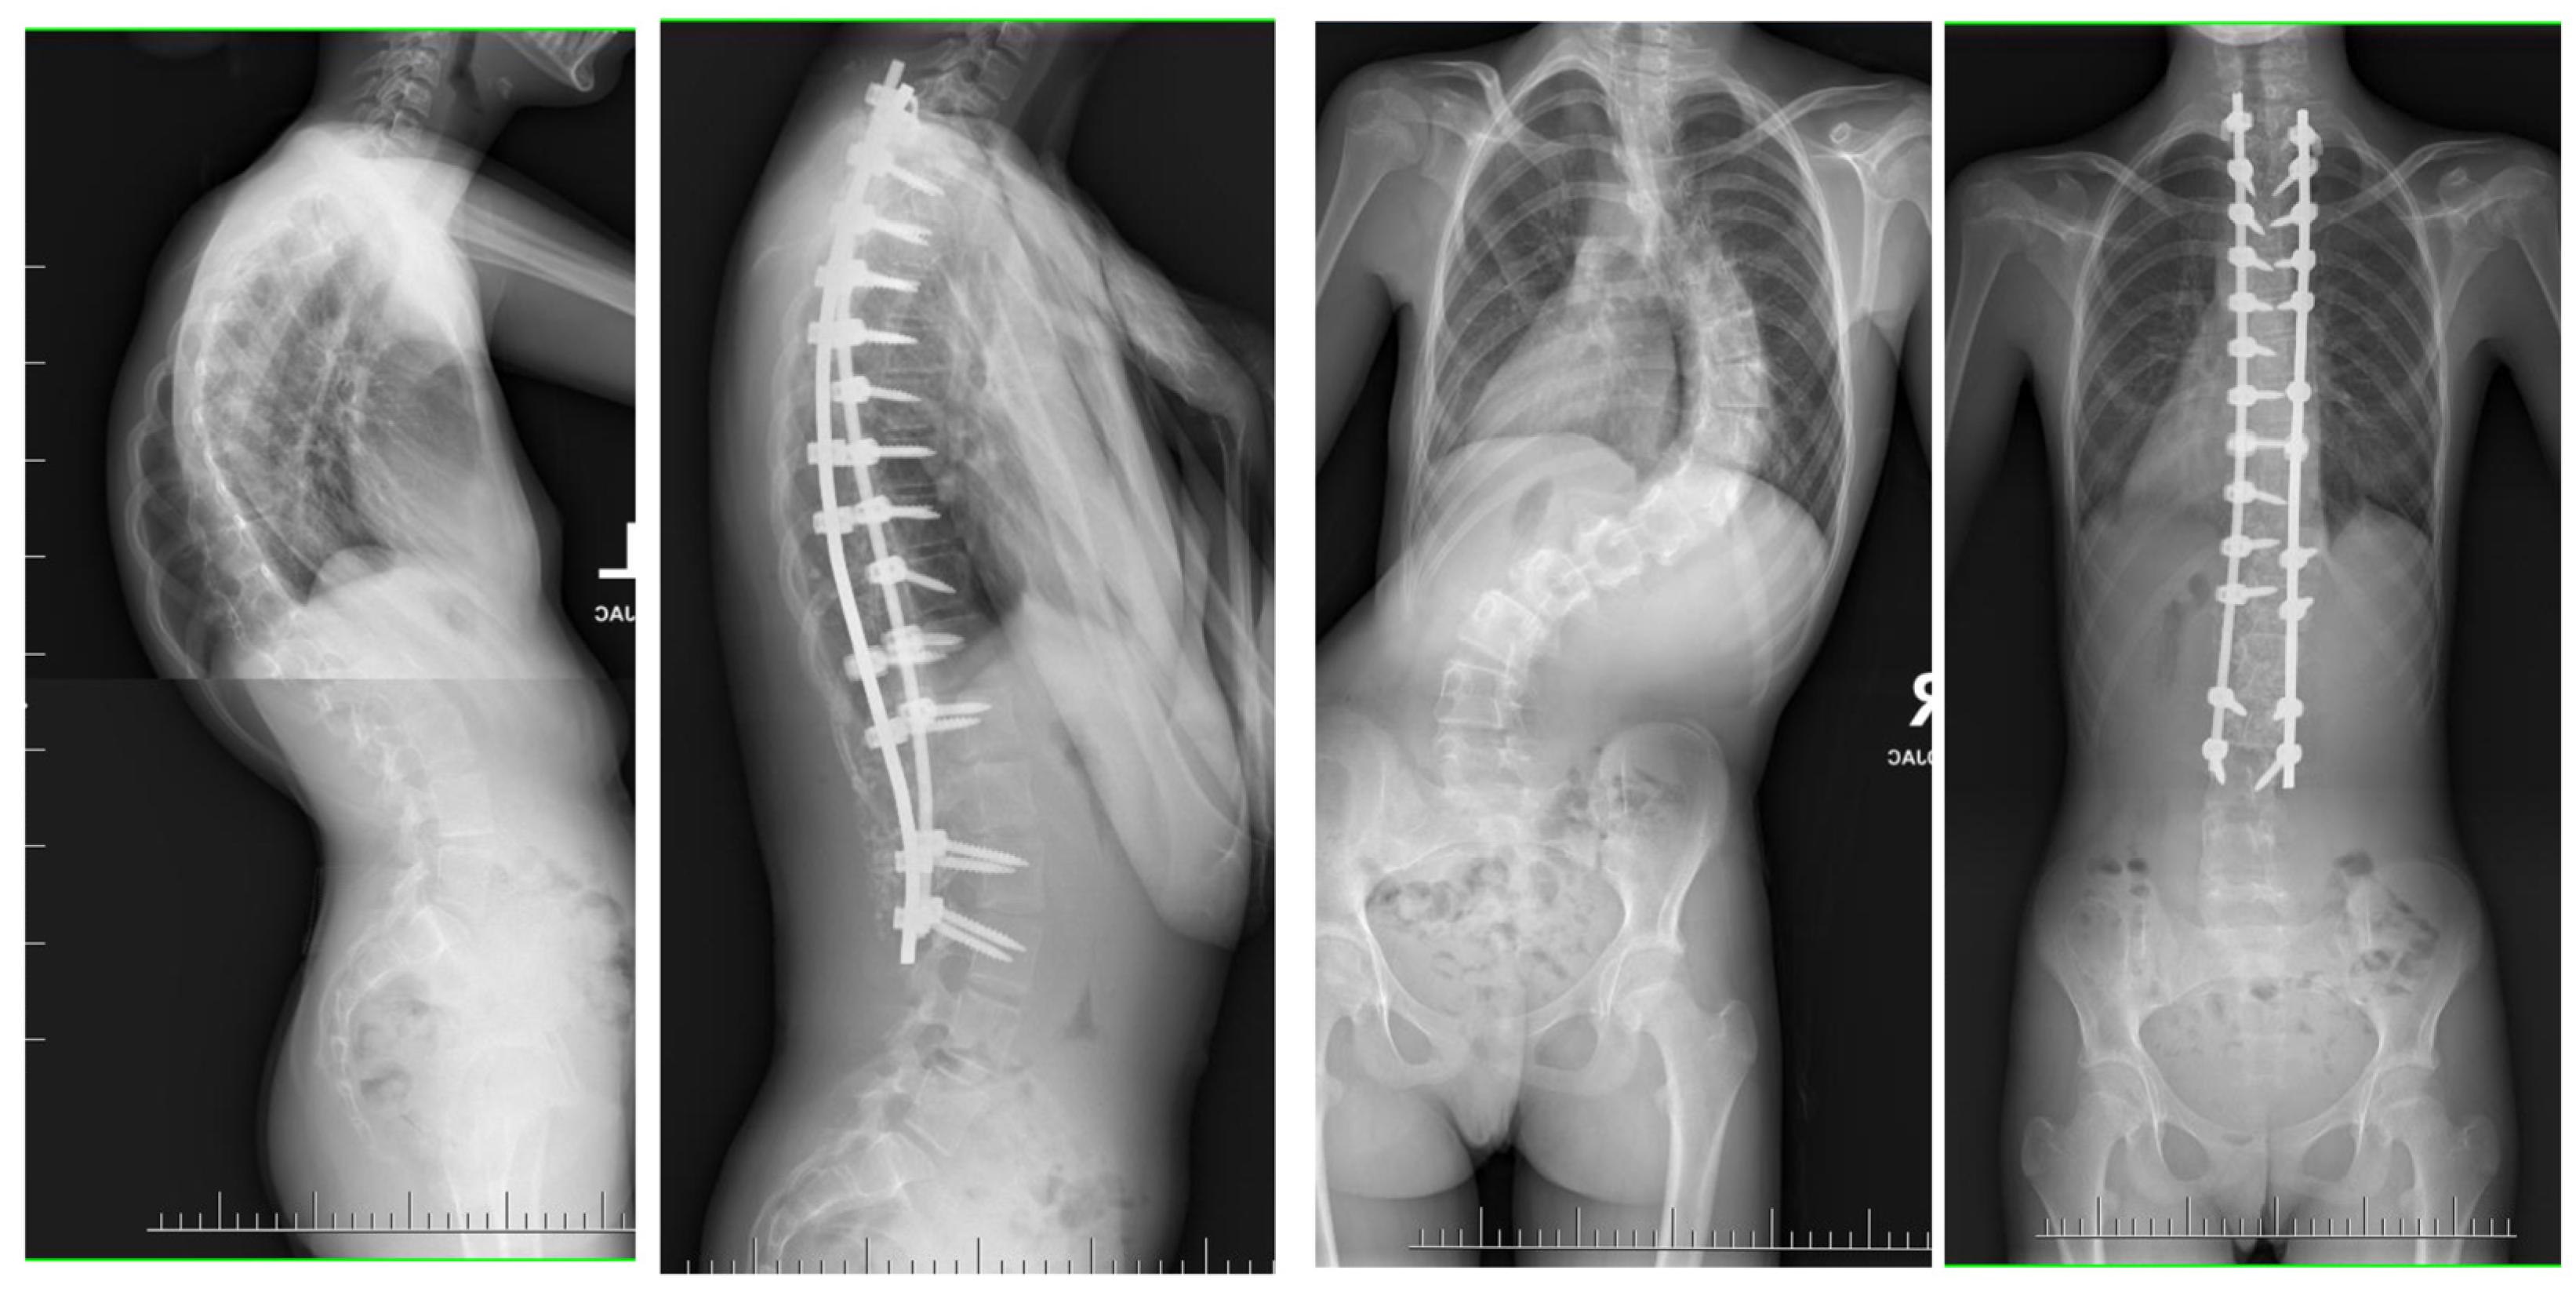

Large spinal deformities, especially those originating from underlying neuro-muscular conditions or severe lumbar scoliosis, can pose a significant challenge when it comes to dealing with pelvic obliquity [62,63]. The presence of pelvic obliquity can lead to incorrect sitting posture and persistent pressure ulcers, making it a crucial issue to address for achieving a positive outcome; nevertheless, it is a task that is often intricate and multifaceted [63]. In the realm of addressing pelvic obliquity, intraoperative halo traction (HT) emerges as a valuable adjunct for improving the correction of this condition. A research study involving a cohort of 40 patients with neuromuscular scoliosis who underwent posterior spinal fusion with an extension of fixation to the pelvis highlighted that 20 of these patients were subjected to intraoperative HT [62]. The initiation of HT took place subsequent to the induction of anesthesia, with each halo being firmly secured by four pins. Following this, a sturdy Kirschner wire was carefully inserted through the distal femur on the side exhibiting the elevated hemipelvis. Upon assuming the prone position in the conventional manner, a traction of 6.8 kg was applied to the halo, which was then gradually escalated to an average of 11.3 kg until the pelvis achieved the desired alignment. The outcomes of this intervention indicated a notable 78% correction in pelvic obliquity within the HT group, in contrast to 52% in the control group [62]. Similarly, a detailed case report by Huang et al. illustrated the successful rectification of severe pelvic obliquity through the implementation of intraoperative HFT [63]. A separate study by Hamzaoglu et al. delved into the cases of 15 patients with thoracic scoliosis who underwent a treatment regimen involving intraoperative HFT in conjunction with posterior-only instrumentation [58]. Unlike prior analyses, HFT was not specifically employed for addressing pelvic obliquity in this scenario. The established protocol entailed obtaining a pre-operative traction radiograph while the patient was under anesthesia, resulting in an average enhancement of 51% in the major thoracic curve. In instances where the curve did not exhibit adequate correction, extensive facet resection and posterior release procedures were carried out. Noteworthy investigations focusing on intraoperative HFT have not documented any complications linked to traction [59]. Owing to the transient nature of the traction utilized, issues commonly associated with pre-operative traction, such as infections at the pin sites or loosening, are anticipated to be less prevalent in occurrence. Barsoum et al. chronicled a case involving an adult patient who was subjected to 2.3 kg of traction using Gardner-Wells tongs, and subsequently experienced a post-operative cranial nerve VI palsy [61]. However, reassuringly, this neurological impairment was completely resolved during the 6-month follow-up evaluation. Figure 4 shows X-rays of a 14-year-old girl treated with intraoperative halo-femoral traction.

Figure 4.

Radiographs taken before and after surgery at the last follow-up appointment depicting a 14-year-old female with severe adolescent idiopathic scoliosis who underwent intraoperative halo-femoral traction, followed by multi-level Ponte osteotomy and posterior spinal fusion in a single-stage surgical procedure.